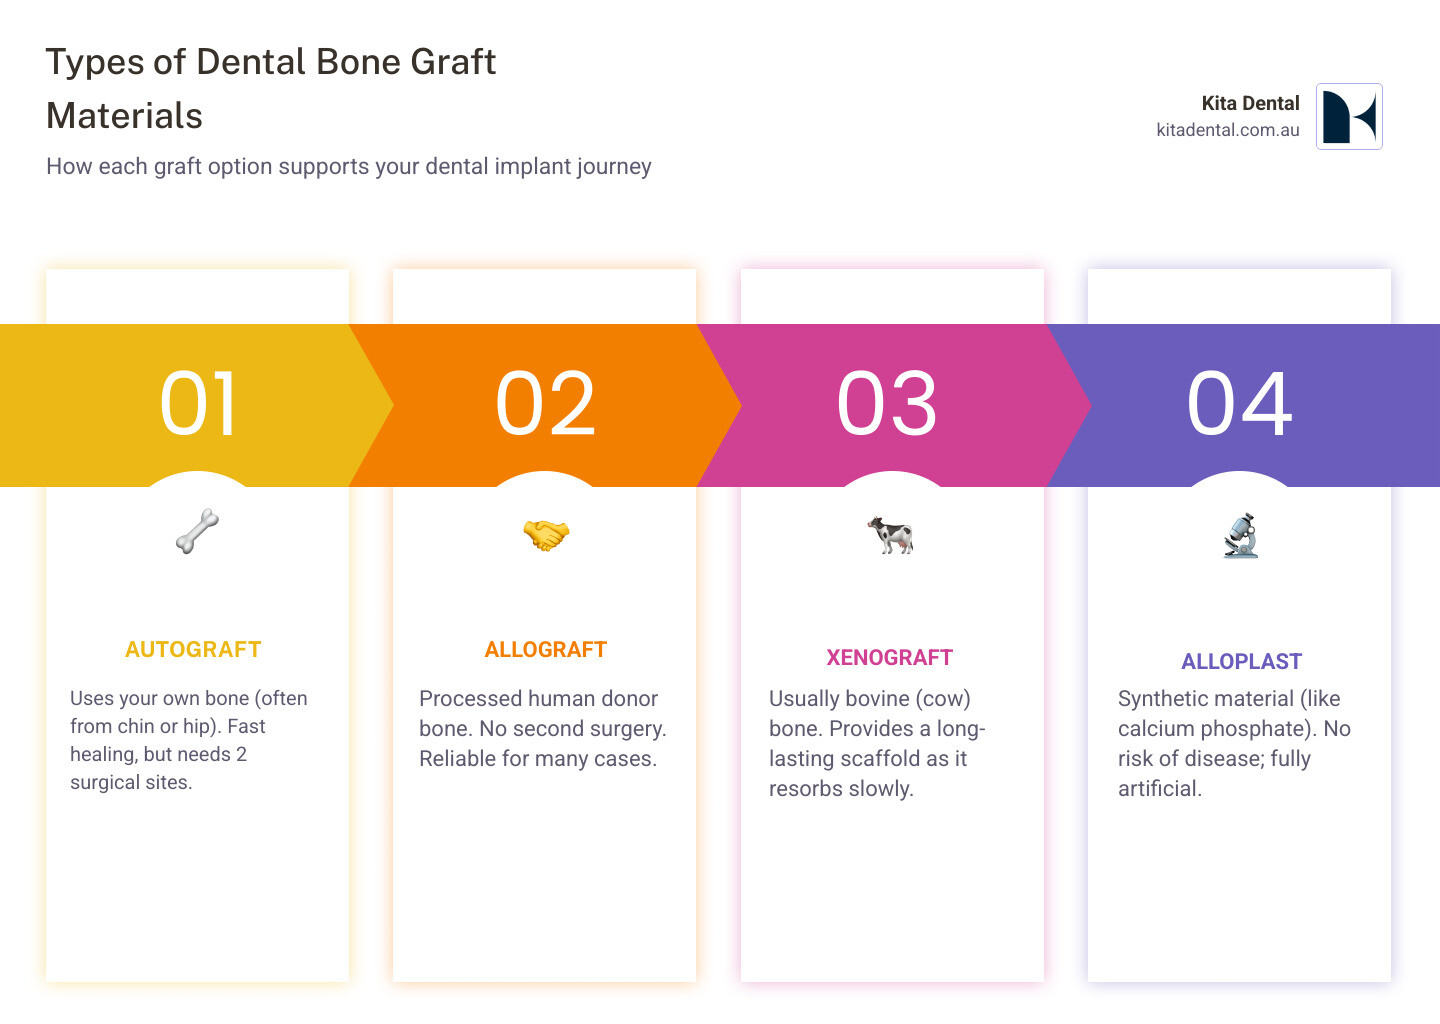

When it comes to bone graft dental implant procedures, we have several excellent material options. Autograft uses your own bone, typically harvested from another area of your jaw. Allograft comes from carefully processed human donor bone. Xenograft uses animal-derived bone (usually from cows) with all organic material removed. Finally, synthetic materials are engineered to mimic natural bone properties.

Types of Bone Graft Materials & Common Procedures

Choosing the right bone graft material is like selecting the perfect foundation for your home – it needs to match your specific situation and provide reliable, long-term support.

Autograft materials remain the gold standard because they use your own bone tissue. We typically harvest this from areas within your mouth, such as your chin or wisdom tooth sites. The beauty of autografts lies in their living bone cells and natural growth factors, which promote the fastest healing.

Allograft materials offer an excellent alternative without the need for a donor site on your body. These processed human donor bones undergo thorough sterilization while preserving the mineral structure that your body recognizes and accepts.

Xenograft materials, primarily derived from bovine bone, provide another reliable option. Through careful processing, all organic components are removed, leaving behind a mineral scaffold that closely resembles human bone structure.

Synthetic materials eliminate any concerns about disease transmission. These materials are completely artificial yet biocompatible, using advanced ceramics and calcium compounds.

We can improve any graft material with Platelet-Rich Plasma (PRP), which concentrates your own platelets and growth factors to potentially accelerate healing.